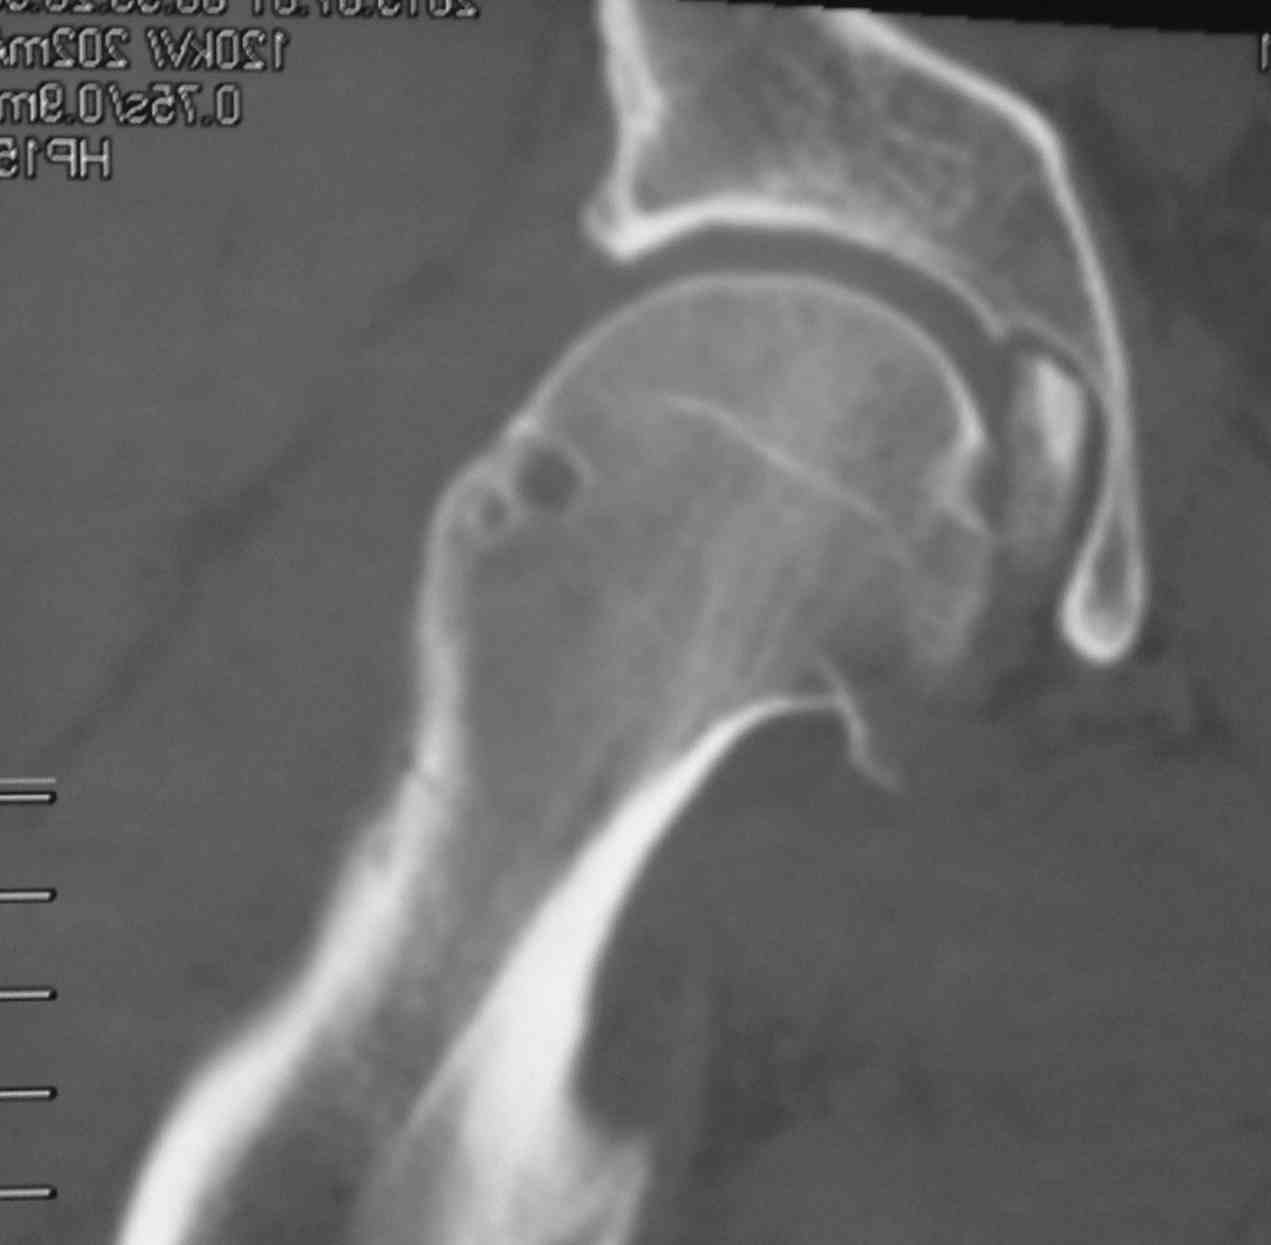

[Ortho] перелом проксимальной тибии + вывих бедра

Высокоэнергетическая травма около недели назад, мужчина 39 лет

По месту поступления вывих бедра вправлен, ПХО раны открытого перелома

б/б кости, скелетное вытяжение. В настоящее время рана заживает неплохо,

небольшое количество серозно-геморрагического отделяемого, состояние

мягких тканей неплохое. Планируем остеосинтез плато из 2-х доступов по

заживлению раны.

2 часть задней стенки в суставе, такое впечатление, что она больше ямки

и подвывихивает сустав или это ошибочное впечатление?

3. насколько целесообразно искать этот фрагмент во впадине и пытаться

засинтезировать задний край при наличии довольно выраженного FAI?

Попробовать при вывихе полечить и то и другое (практического опыта

лечения FAI нет, шаблонов для головки тоже, артроскопия т/б недоступна)?